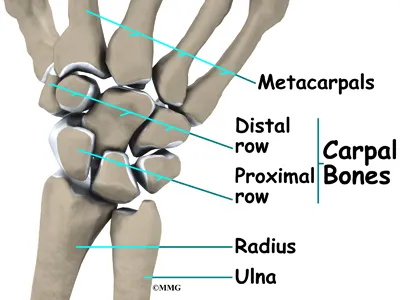

Triangular fibrocartilage complex (TFCC) injuries affect the ulnar side of the wrist—the side closest to the little finger. Mild cases may feel like a simple wrist sprain, but due to the complexity of the wrist’s soft tissues, these injuries can significantly impact stability and function.

The TFCC plays a crucial role in supporting and stabilizing the wrist joint, allowing smooth and controlled movement. When this structure is damaged through trauma or gradual degeneration, it can lead to persistent pain, weakness, and limited mobility.